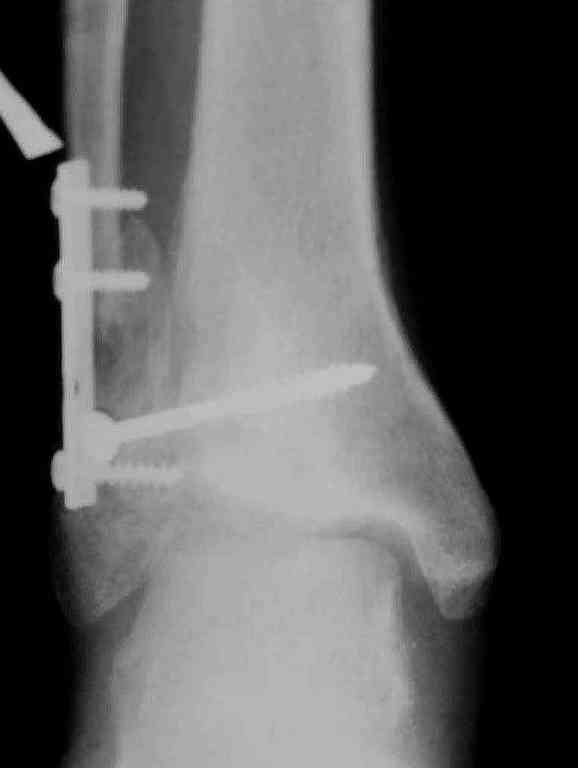

Вторая пациентка 34 лет, перелом получала в Испании, где от операции отказалась, дома по приезду сняла скотчкаст и лечилась у костоправов, нагрузка с 3 недели. Операция через 3 мес после травмы. Остеотомия м-б кости, фиксация пластиной, восстановление МБС. Так как медиальная лодыжка подтянулась, суставная щель на ЭОП контроле нормализовалась ограничились латеральным доступом. Реконструкцию заднего края не пытались сделать тк там уже прослеживалась консолидация, а сминать эпиметафиз не хотелось. В настоящее время ходит с тростью \три месяца после операции\, сустав нестабилен-слабость дельтовидной связки. Супинатор и плотные кроссовки дают возможность длительно ходить. Первый снимок сделан в Испании после репозиции, второй через 2 месяца после травмы перед операцией, третий-через 3 мес после операции.

Спасибо за вложенную схему , ранее она нам не попадалась.Согласен с Алексеем, что в обоих случаях не удалось восстановить длину фибулы.По вопросу о МБС, в первом случае после 8 месяцев синдесмоз был выполнен плотной рубцовой тканью, которую необходимо было убрать для репозиции фибулы в вырезку и винт действительно был введен с компрессией, во втором случае МБС не открывался и компресии не задавлось.Может дистрофия эпифиза все же следствие 5 месячной нагрузки с нестабильным суставом и компрессии тараном, тк вес пациента достаточно высок. По второму наблюдению необходимо определиться с тактикой, при пронации стопы отчетливо определяется слабость дельтовидной связки-перерастянута ходьбой в нестабильном суставе? Показана ли надлодыжечная варизующая остеотомия?

Как отметили коллеги, в обоих наблюдениях не были достигнуты цели восстановления, игнорирован основной принцип, длина малоберцовой, без которой всякие попытки обрешены на провал.

По снимкам в первом случае, укорочение малоберцовой приблизительно около 8-10 мм. Удовлетворительным восстановлением длины малоберцовой считается, когда на снимке суставная щель равны со всех сторон.